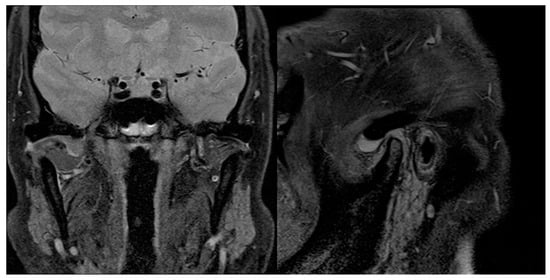

Figure 9.

Preoperative sagittal and coronal MRI scans showing, on the right, TMJ joint effusion and LBs, but no bony involvement.

Figure 10.

The 6-month postoperative sagittal and coronal MRI scans showing no signs of relapse on the right TMJ.